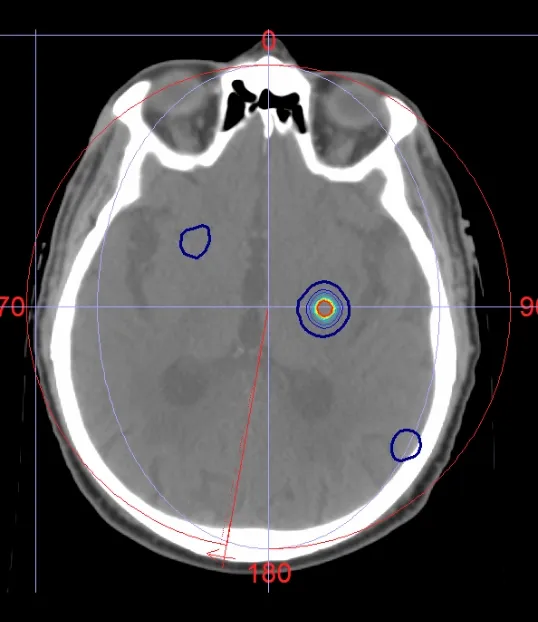

Figures 1-10 SBRT for brain metastasis. The patient previously received 30 Gy in 15 fractions of whole brain irradiation, now presenting with nine distinct brain mets scattered throughout the brain.

The images show very conformal dose distributions around each lesion achieved with Monaco treatment planning and Versa HD delivery. This patient received 30 Gy in 5 fractions to all nine mets.

The dose distribution showcases the ability of Elekta products to tightly conform dose to targets and spare previously irradiated areas while minimizing the risk of adverse effects.